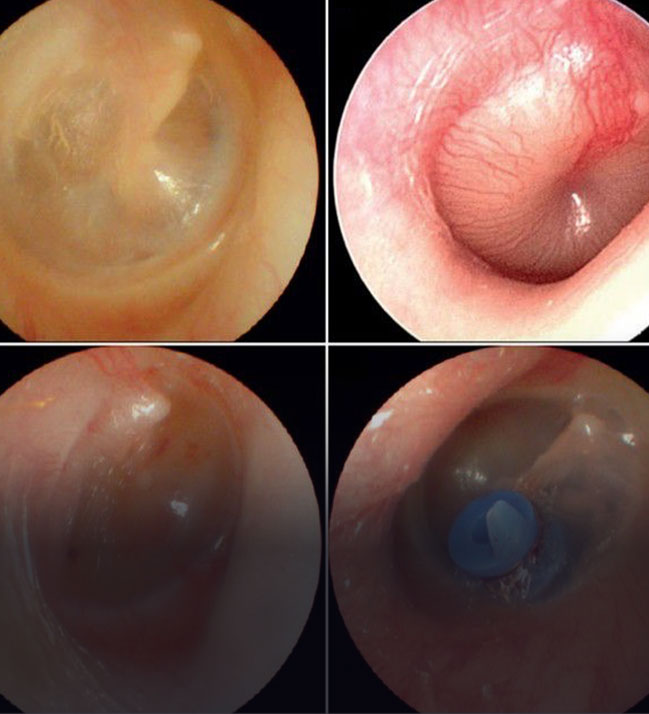

Çocuklarda Seröz Otit

Kulakta Sıvı Birikmesi